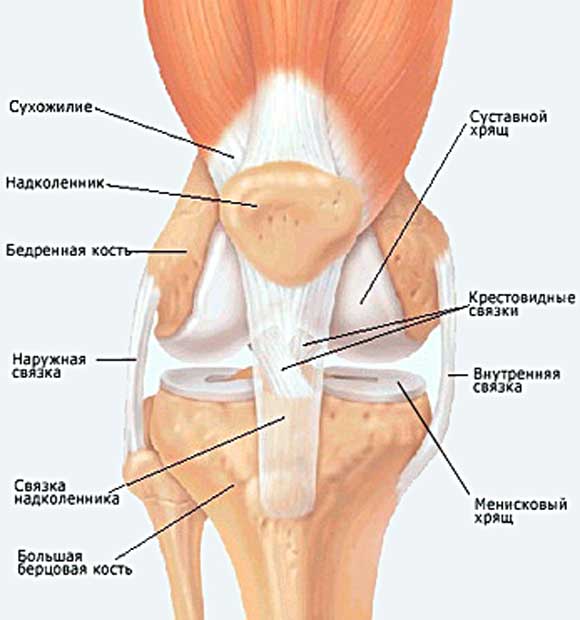

занималась по Дж Майклз примерно 6 недель (чередовала пресс и 30 дневку), начали болеть колени, сильно уже где то на 3 уровне 30 дневки (до этого тоже болели, но терпимо), причем то одна, то другая, естественно продолжать я не стала, мазала согревающей мазью, бинтовала, вроде все прошло, кроме боли под коленкой, если растягиваюсь (кстати с ней что делать ? ). Вобщем сегодня решила начать бегать и болит коленка где то сбоку , как я поняла по картинке наружная связка. Боль достаточно сильная, но видимо занимает совсем мало "места" ( точечная ) и более менее терпимая. Так вот вопрос : что с этим делать ? у кого такое было, как лечились?